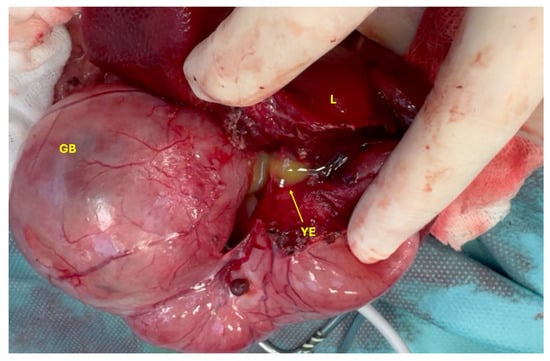

The cat was placed in dorsal recumbency, clipped, and aseptically prepared for surgery. Following clipping, the extent of the cranial abdominal enlargement was visible (Figure 3). Abdominal exploration revealed a markedly dilated gallbladder and CBD measuring approximately 10 × 7 cm, as well as hepatic ducts with an average diameter of 8 mm (Figure 4). The anatomical distinction between the gallbladder, cystic duct, and the CBD was no longer discernible. Additionally, the junction between the CBD and the duodenum at the level of the major duodenal papilla was severely dilated (Figure 5).

Both the gallbladder and CBD were filled with yellow exudate (a mixture of pus and bile), which began to leak from the liver upon initiation of dissection (Figure 6). Severe inflammation of the right arm of the pancreas was noted, along with dilation of the main pancreatic duct, which also contained yellow exudate. The stomach was empty and compressed, likely due to the mass effect exerted by the dilated gallbladder and CBD.

Figure 6. Yellow exudate (YE) from the gallbladder (GB) and liver (L).